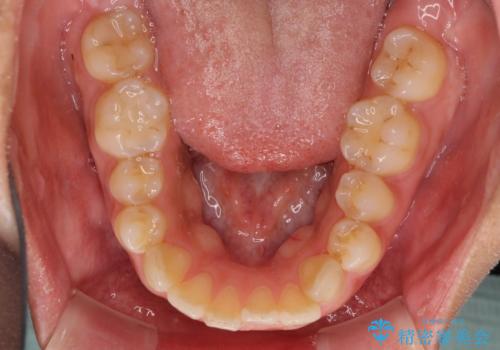

- 上下の前歯のでこぼこを気にして来院された患者様です。

結婚式が近いこともあり、全く目立たない裏側矯正により口元を整えることとしました。

下顎が左側にずれているため、裏側矯正ということもあり咬み合わせを整えるのに時間がかかってしまいました。